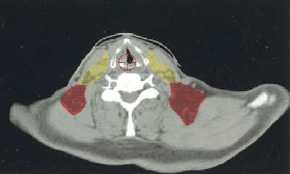

(a–l) Marked lymph nodes (LNs) with each LN group separated by color.

Light blue, submental LN (Ia);

dark blue, submandibular LN (Ib);

yellow, jugular LN (II, III, IV);

red, spinal accessory LN (V);

light green, retropharyngeal LN;

orange, parotid LN;

dark green, anterior jugular LN (VI);

pink, retroauricular/occiptal LN.